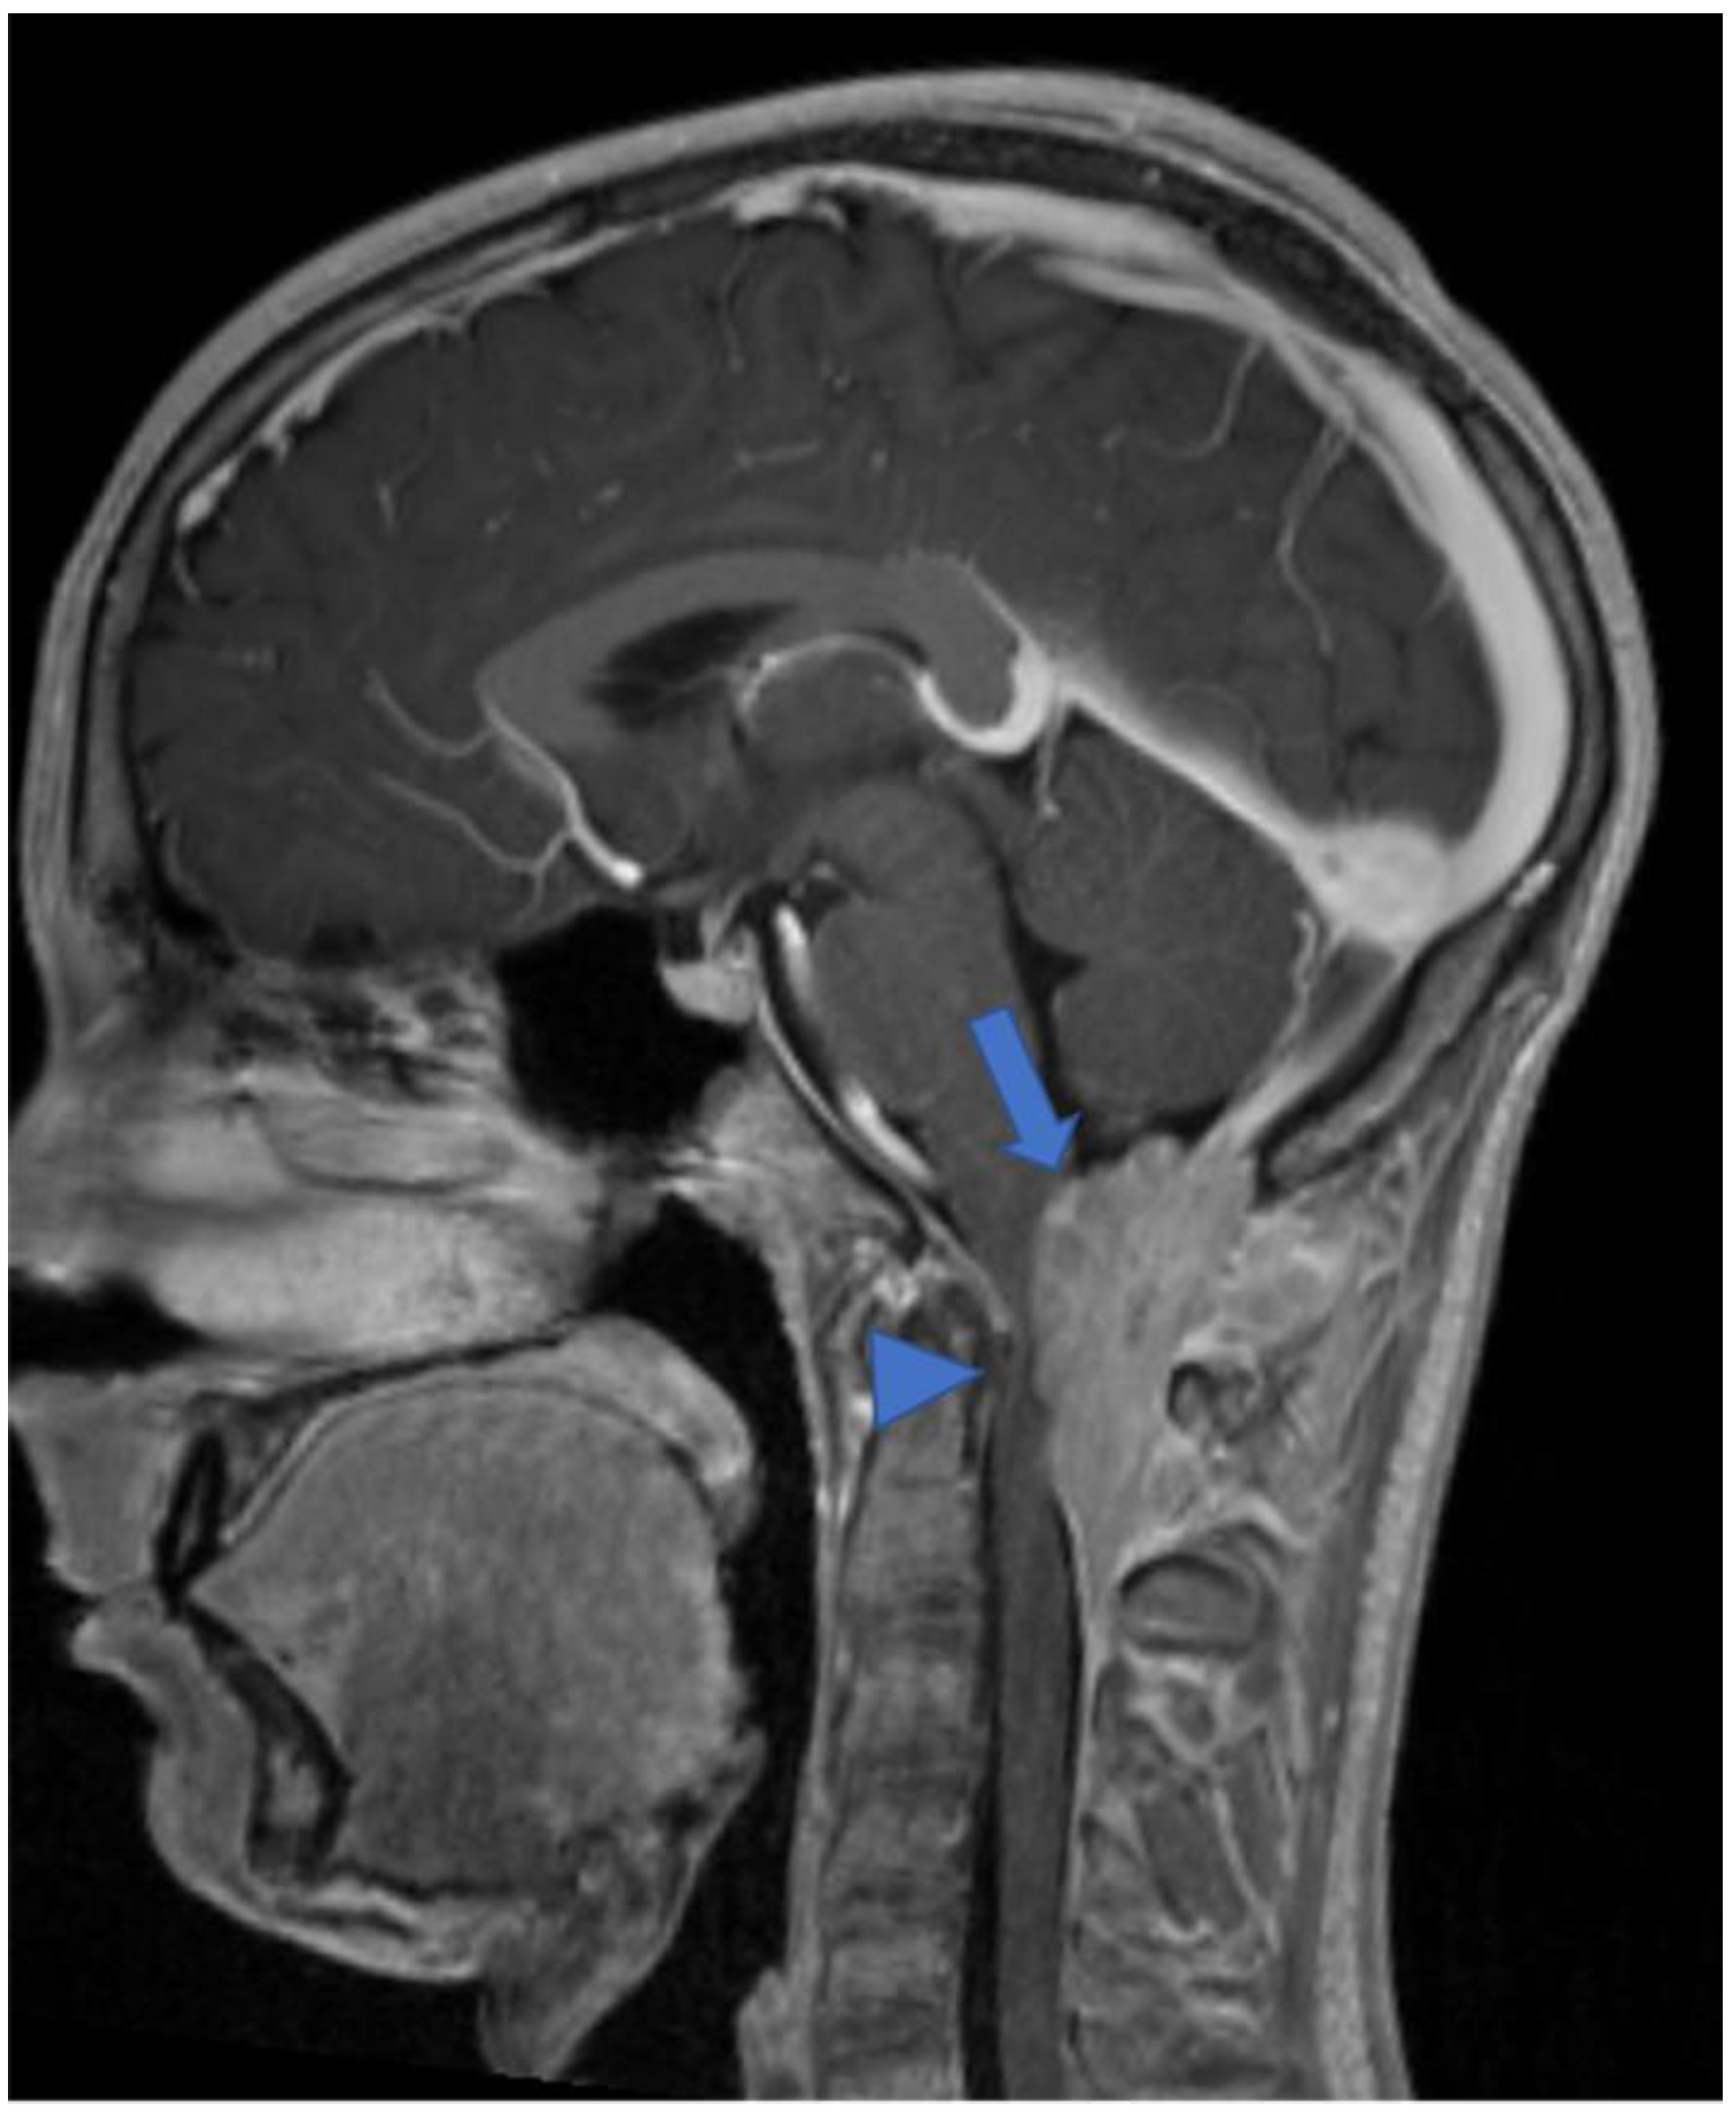

2.2. Diffuse Leptomeningeal Glioneuronal Tumor